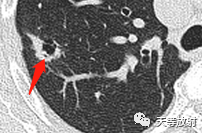

右肺上叶结节影,周围更小结节,形态不规则,胸膜面相对干净。